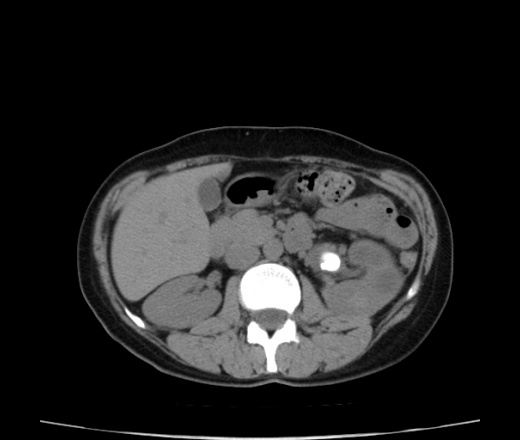

Конкременты почек кт

Конкременты почек кт 104 фотографий